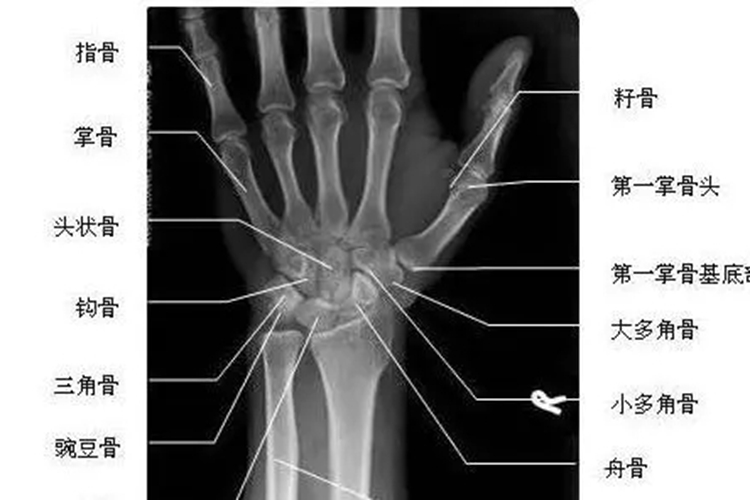

腕关节正位X线片

腕关节正位X线图像范围包括近侧掌骨、远段尺桡骨,以及腕部内、外侧软组织。尺桡骨远端及诸腕骨呈正位影像,尺桡骨远侧平行排列无重叠。豌豆骨与三角骨、大多角骨与小多角骨重叠,舟状骨缩短。桡腕关节、掌腕关节及腕骨间关节外侧关节间隙呈切线位置,关节面显示清楚。腕部诸骨(舟骨、三角骨、豌豆骨、大多角骨、小多角骨、头状骨及钩骨等)骨纹理清晰显示,关节间隙及软组织显示良好。